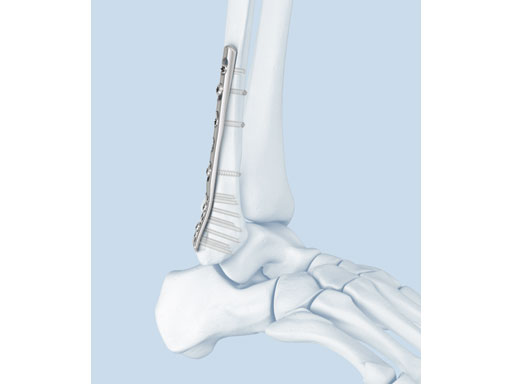

The LCP posterolateral distal fibula plate offers six round locking holes and two coaxial holes distally which accept 2.4 and 2.7 mm locking and cortex screws to provide multiple screw options. The distal holes are slightly divergent to help prevent screw pullout. The coaxial hole accepts both locking and cortex screws and its recess for screw heads minimizes screw-head prominence by allowing the screws to sit more flush with the plate, creating a low-profile construct. Its posterolateral position allows it to be placed deep to the peroneal muscles, minimizing the risk of wound healing problems due to prominence. A 2.7 mm lag screw may be placed through the distal screw cluster, and a syndesmotic screw may also be placed through the plate.

The anatomically precontoured plate shaft is only 2.25 mm thick yet substantially stronger than the one-third tubular plate. The combination holes in the shaft accept 3.5 mm locking screws, 3.5 mm cortex screws, and 4.0 mm cancellous bone screws.

A 56-year-old man slipped and fell, sustaining a fracture dislocation of the ankle. His fibula was stabilized with a posterolateral plate. The construct included several nonlocking screws in the diaphysis, and multiple 2.7 mm locking screws in the distal fibula. As with most Weber B fracture patterns, a lag screw was possible from posterior to anterior through the plate. Finally, intraoperatively the patient was found to have a syndesmotic injury, and after reduction, a syndesmotic screw was placed through the plate.